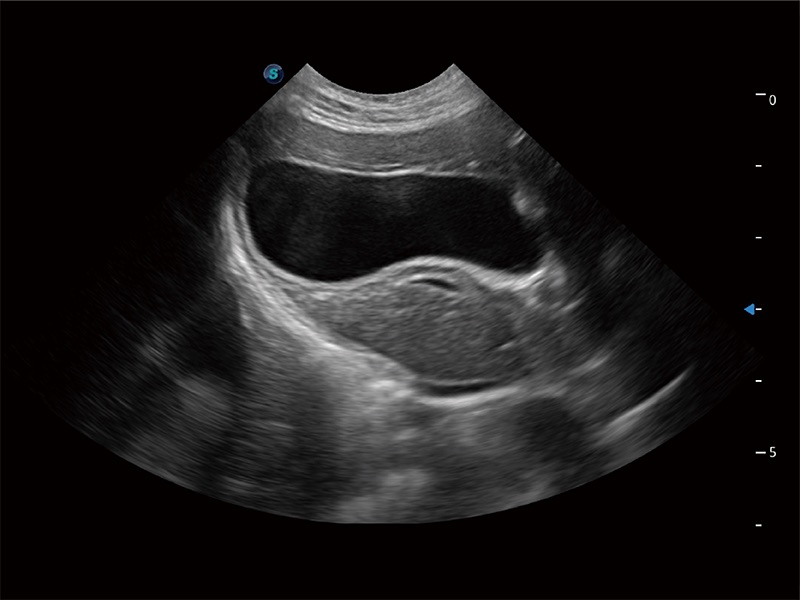

一键自动识别膀胱壁及自动测量膀胱容积,不受膀胱形状和大小的限制,帮助医生快速精准获得测量的数据。

为精细结构及组织边缘提供高清晰度的图像和更大的成像视野。帮助减轻医生的用眼疲劳,快速精准获得测量的数据。